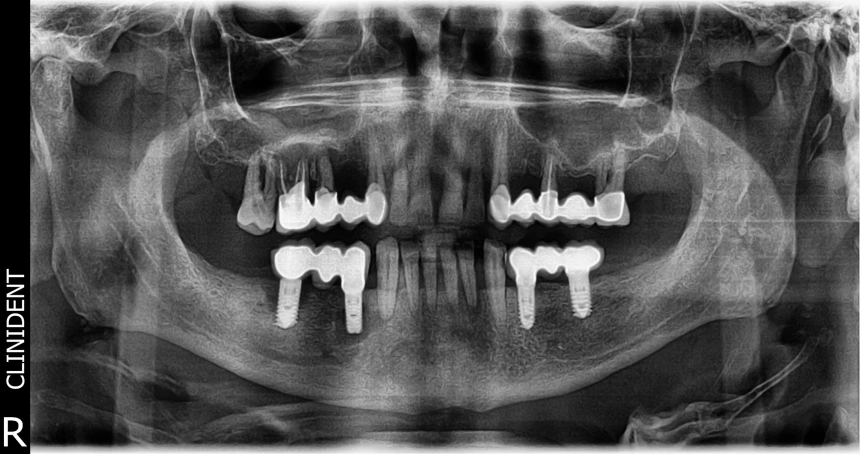

A röntgenkép által mutatott estben páciensünk körülbelül 6 évig nem látogatott vissza klinikánkra, miután elkészültek az új fogpótlásai. Alul, a kihúzott fogak helyére, implantátumokra épülő hidakat kapott.

A sok év kihagyás után, egészségügyi problémák miatt jelentkezett nálunk, immár góckutatásra. A felvételen jól látható az állapotromlás, mely az egész szájüreget érinti.

- Fogágybetegség ütötte fel a fejét, a legtöbb fog gyökere szinte alig van a csontban.

- A hiányos szájhigiénia, a szűrővizsgálatok és fogkőeltávolítások mellőzése miatt a gyulladást okozó baktériumok megtámadták a tartószöveteket, az ínyt és a csontot is.

- Veszélybe kerültek az implantátumok. Ezt az implantátumok csúcsa körüli sötét „üreges” terület jelzi, de ugyanígy a foggyökér körüli gyulladások is jól láthatóvá válnak.

- A gócokból kiszabaduló baktériumok veszélyt jelentettek más szervekre is, ami magyarázatot adott a páciensünk egyéb testi tüneteire.

- Szükség volt több fogának- és a jobb alsó implantátumainak (a röntgen kép bal oldalán láthatók) eltávolítására, a fogágybetegség megfékezésére is. Parodontológus és szájsebész is kezelte a pácienst.